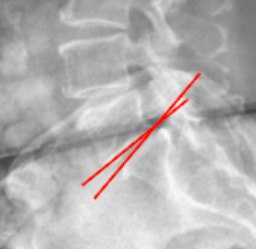

George’s Line (Posterior Vertebral Body Line)